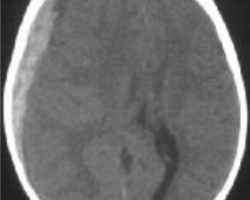

Garçon de 5 mois et demi

Amené par sa mère pour somnolence, pleurs et refus alimentaire

Hypotonie globale + déficit du membre supérieur gauche

Fontanelle bombante